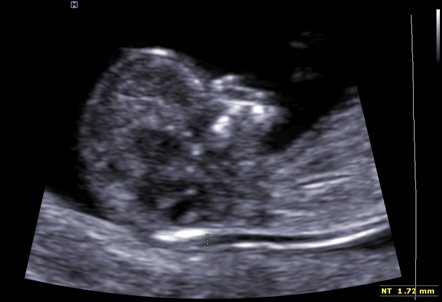

Screening Downova syndromu lze provádět mnoha různými způsoby. V současné době je celosvětově za nejvhodnější metodu screeningu považován takzvaný prvotrimestrální screening Downova syndromu, který se provádí v 11. až 14. týdnu těhotenství a skládá se z vyšetření krve matky a ultrazvukového hodnocení výskytu znaků (markerů) této chromozomální vady u plodu.

Nejvíce je rozšířen prvotrimestrální screening takzvaným kombinovaným testem (v České republice také nazývaný NT screeningový nebo NT plus test), který umožňuje zachytit přibližně devadesát procent plodů postižených Downovým syndromem. Odborník, který provádí prvotrimestrální screening takzvaným kombinovaným testem, by měl být dle doporučení České gynekologicko-porodnické společnosti (a stejně i dle doporučení většiny světových center) takzvaně FMF certifikován na vyšetření NT (šíjové projasnění). Riziko Downova syndromu by po vyšetření mělo být tímto lékařem vypočítáno prostřednictvím FMF certifikovaného počítačového programu (Astraia). FMF je Nadace fetální medicíny se sídlem v Londýně (Fetal Medicine Foundation).

Při prvotrimestrálním screeningu Downova syndromu kombinovaným testem se riziko Downova syndromu vypočítává z:

– věku matky,

– stáří plodu,

– množství tekutiny nahromaděné v podkoží v oblasti záhlaví plodu (velikost „nuchální translucence“) – viz obrázek,

(Foto: MUDr. Veronika Frisová, Profema)

– hladině koncentrace dvou hormonů v krvi matky (ß-hCG & PAPP-A).